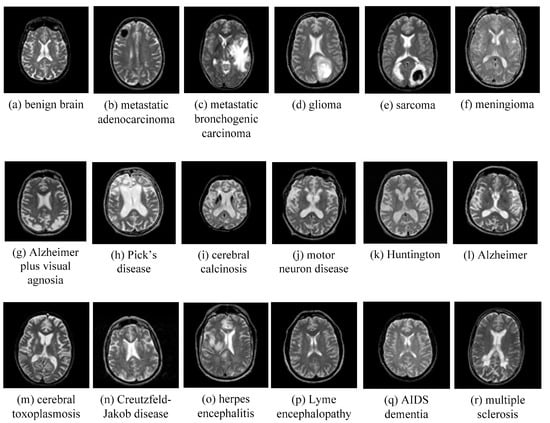

AANLIB: There are many T2-weighted MRI brain images in the image dataset. The images have higher resolution. Because T2 images have higher contrast and clearer vision than T1 modalities, we choose the T2 model for this type of data set. This dataset of the MRI image of the malignant brain is comprehensive. The sample images of disease are shown in Figure 11.

We selected five images from the dataset randomly, which included 17 types of malignant brain images and a benign brain image. The chosen five images contain four brain diseases and a benign one. That is, we select 5 × ( 1 + 17 ) = 90 images to form a brain MRI image dataset.

Figure 11. Sample of brain MRIs.

Entropy 20 00964 g011